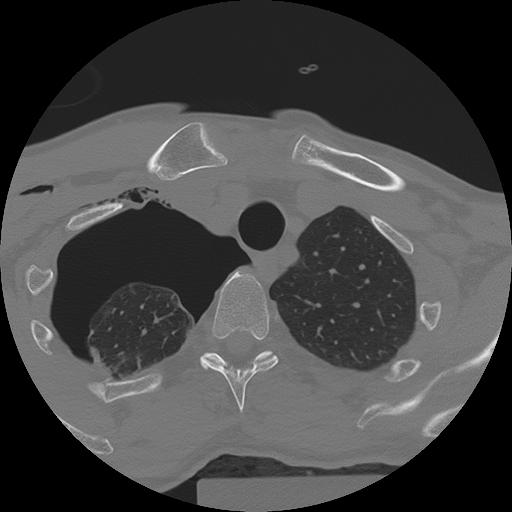

11 HUESO,,Axial,2.0,HUESO,,